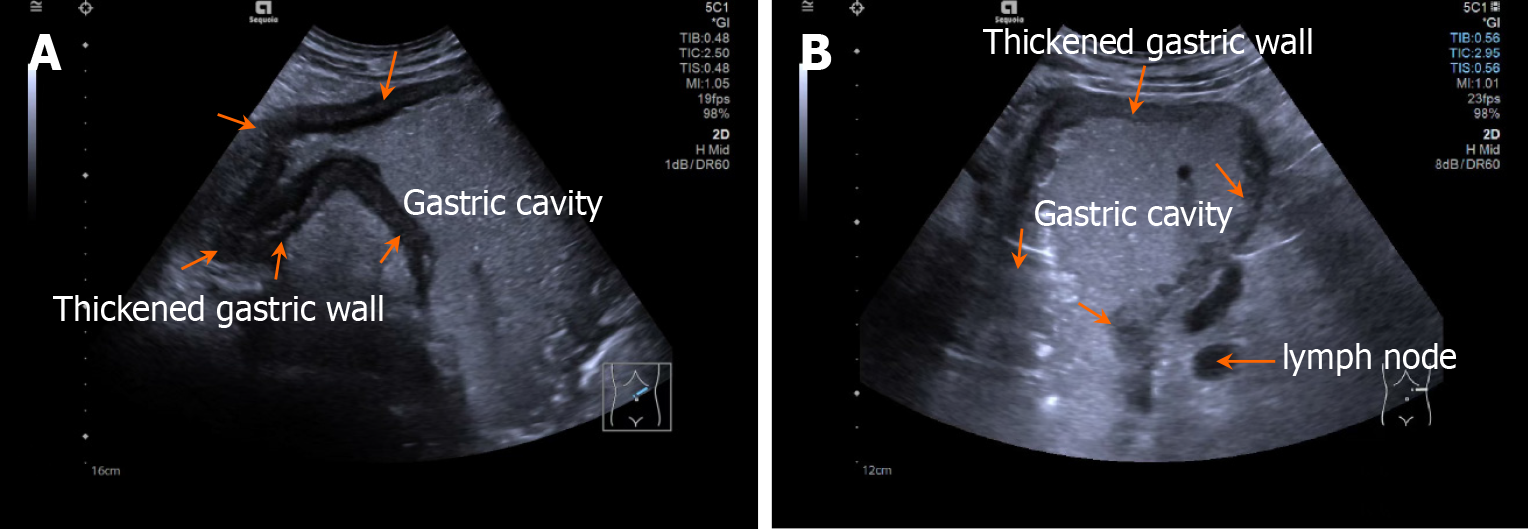

Patients fasted for > 8 hours and orally ingested 500 mL of prepared gastrointestinal contrast ultrasonography agent (Huzhou Dongya Medical Supplies Co., Ltd., Zhejiang; medical device registration number 20212060179) 5 minutes before the examination using a Siemens-SEQ1 color ultrasonography diagnostic device (registration number: National medical device registration import 20192060012) for gastrointestinal contrast ultrasonography. During the examination, the patient was adjusted to different positions, including supine, left and right lateral decubitus, and semi-sitting, with an appropriate amount of ultrasonography coupling agent applied. A probe was used to perform multi-plane scanning of the digestive tract from the cervical esophagus to the duodenum, with frequency and mechanical index set at 2-4 MHz and 0.07, respectively. After the basic contour structure of the stomach was clearly displayed, the thickness of the gastric wall, peristalsis, and the distribution of contrast agent in the gastric cavity were observed in detail. Representative images are shown in Figures 1 and 2.